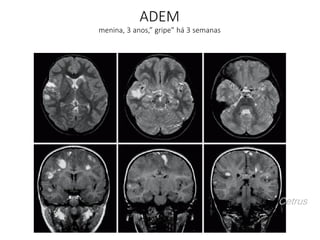

ADEM – Encefalomielite Aguda

Disseminada

• Ressonância Magnética

– Hiper T2 e FLAIR

– Substância branca

subcortical e profunda

– Hemisférios cerebrais

– Cerebelo

– Tronco

– Medula

– Tálamos e núcleos da base

• Grandes e confluentes

(pseudotumorais)

• Pouco efeito expansivo

• Bilaterais e assimétricas

• Realce variado

– 30% nodular ou heterogêneo

• Lesões diminuem após

tratamento com esteróides

• Sequelas: 10 a 20 % dos casos

- convulsões recorrentes

ADEM

menina, 3 anos,” gripe” há 3 semanas

Cetrus